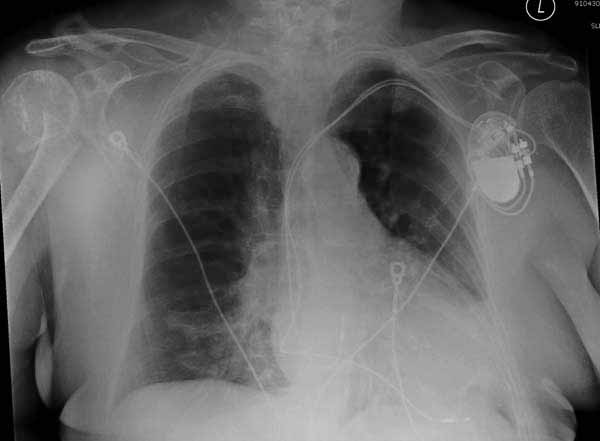

Здесь результат похожего случая, больная 87 лет, отягощенная сердечными делами и два года назад установка pacemaker и нескольких стентов. На третий день, сегодня утром сделали операцию. Послеоперационный псевдовывих связанный с релаксацией мышц и общим обезболиванием.

Имя     : humerus orif ap.jpg

Тип     : image/jpg

Размер  : 23835 байтов

Описание: отсутствует

Url     : http://weborto.net:8080/pipermail/ortho/attachments/20110611/5927b955/attachment-0008.jpg